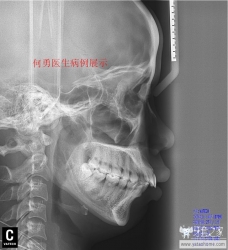

直面型

我们正畸医生追求的理想面型。建议牙套们将Gonzales-Ulloa零子午线和Ricketts审美平面区结合起来判断你是否是直面型。下面用病例展示的方式告诉牙套如何才是直面型。